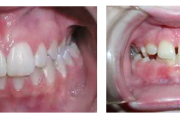

prognaatne hambumus, ülemised eeshambad on ettepoole alumiste suhtes ja eest

progeenne hambumus; alumised eeshambad on ettepoole ülemiste suhtes;

Turritavad ülemised lõikehambad.